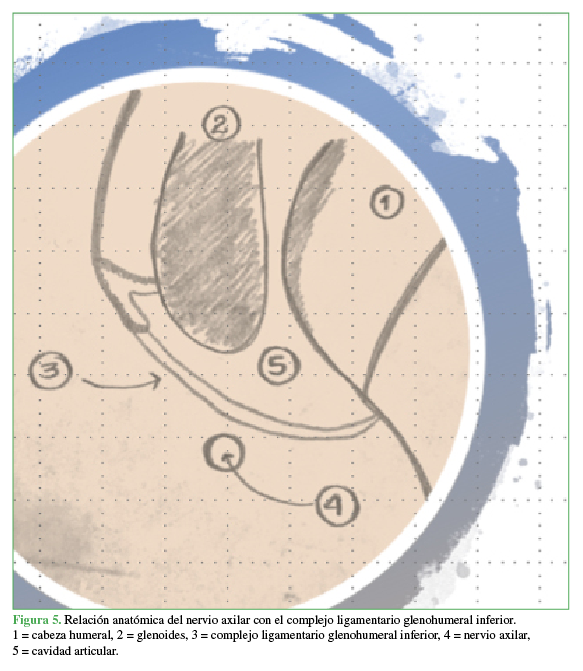

Introducción: La prevalencia del dolor de hombro oscila entre el 6,7% y el 66,7%; los trastornos del manguito rotador y especialmente la ruptura pueden alcanzar una prevalencia del 22,1%. Debido a los importantes avances y estudios en la reparación de esta lesión, la cirugía artroscópica ha permitido una mejor identificación, visualización y clasificación, y un mejor manejo de los pacientes. Además, la ruptura del manguito rotador o la fractura de la tuberosidad mayor del húmero incrementan el riesgo de lesión nerviosa (riesgo relativo –1,9), más significativa en pacientes >60 años. Se presenta a un paciente con ruptura postraumática del manguito rotador, quien requirió reparación artroscópica mínimamente invasiva, con evolución posoperatoria estacionaria y diagnóstico de lesión del nervio axilar, sin recuperación autolimitada atribuida a luxación anterior e inestabilidad secundaria altrauma inicial.Conclusiones: La lesión del nervio axilar es más frecuente que lo esperado y, en muchas ocasiones, la identificación temprana se pasa por alto debido a la alta asociación con otras lesiones. Por lo tanto, el diagnóstico y el manejo oportunos requieren mucho cuidado por parte del médico tratante. AbstractIntroduction: The prevalence of shoulder pain varies between 6.7% and 66.7%; whereas rotator cuff disorders–especially rupture–can reach a prevalence of 22.1%. Due to the important advances and studies in the repair of this injury, arthroscopic surgery has allowed a better identification, visualization and classification, as well as a better handling of the patients. In addition, rotator cuff ruptures or greater tuberosity fractures increase the risk of nerve injury (relative risk -1.9), which is more significant in patients >60 years old. We discuss the case of a patient with post-traumatic rotator cuff rupture who required minimally invasive arthroscopic repair. No weight-bearing was allowed during the postoperative period. Patient presented a non-self-limited axillary nerve injury secondary to anterior dislocation and resulting instability after the original trauma.Conclusions: Axillary nerve injuries are more common than expected and, in many cases, early identification is not possible due to its high rate of association with other injuries. Therefore, treating physicians must be very careful in order to achieve a timely diagnosis and management of the patient.Descargas

Maman E, Morag G, Safir O, Benifla M, Mozes G, Boynton E. The anterior trunk of the axillary nerve: surgical anatomy and guidelines. A fresh, cadavers study. J Orthopaedics 2008;5(2):e7. http://www.jortho.org/2008/5/2/e7

Price MR, Tillett ED, Acland RD, Nettleton GS. Determining the relationship of the axillary nerve to the shoulder joint capsule from an arthroscopic perspective. J Bone Joint Surg Am 2004;86(10):2135-42. PMID: 15466721